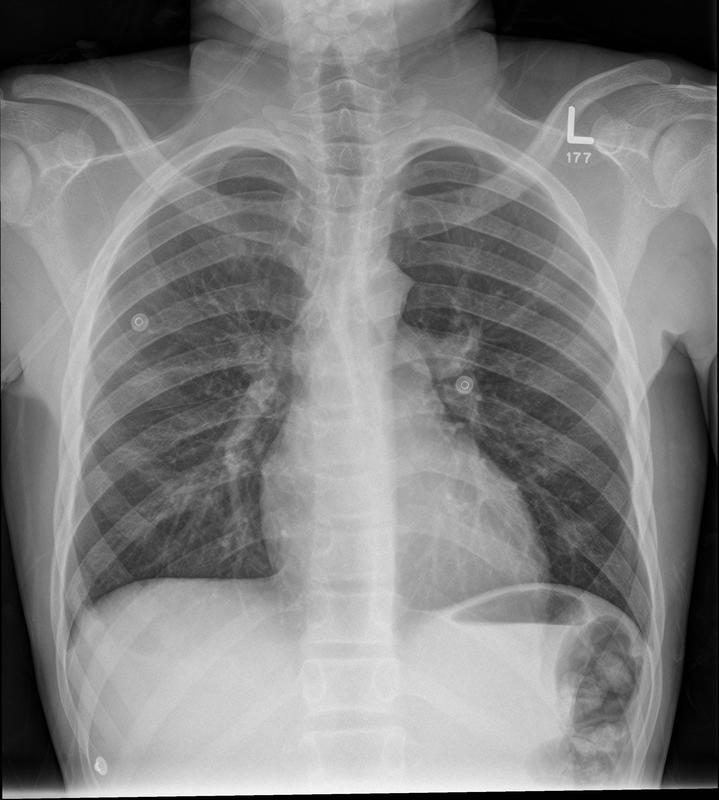

Aortic nipple